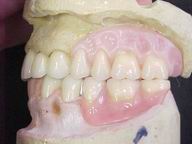

Reabilitação funcional e estética em ambas as arcadas

com próteses fixas e removíveis de encaixe de precisão.

Fase Intermediária Vista Frontal

Vista Oclusal Sobre Modelos de Gesso